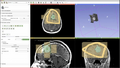

An example implementation of GrowCut has been implemented as a test.

• Topic was generalized to include editor effects based on ITK and VTK

• Porting of CLI tools to run as steered segmenters (Yi, Ivan)